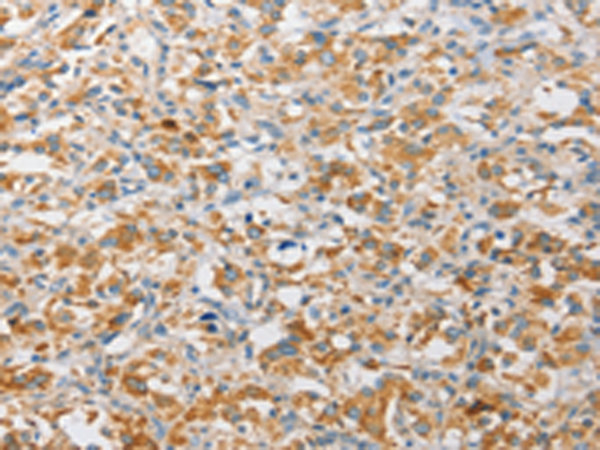

分类: 科研抗体货号: P07869别名: A3G; ARCD; ARP9; ARP-9; CEM15; CEM-15; MDS019; bK150C2.7; dJ494G10.1应用: WB,IHC反应种属: Human